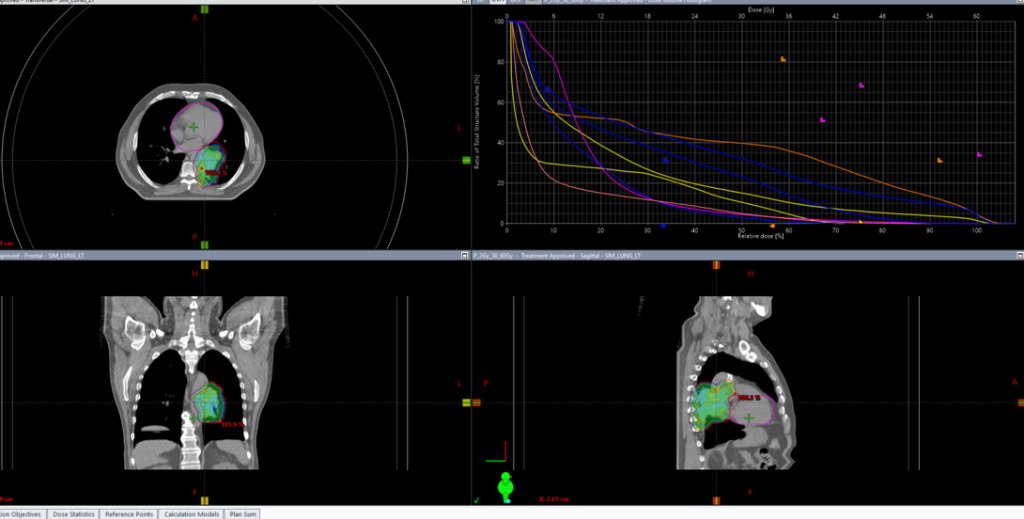

Пациенту рекомендован курс химиолучевой терапии на опухоль легкого и ПЭТ позитивные лимфатические узлы РОД 2Гр до СОД 60Гр на фоне еженедельного введения химиотерапии по схеме карбоплатин + паклитаксел

13.07.2022 выполнена КТ- топометрия органов грудной клетки с толщиной среза 2.5 мм.

Выполнено оконтуривание на КТ срезах объемов мишени (GTV,CTV,PTV) и всех органов риска

КТ – компьютерная томография

21.07.2022 был запланирован первый сеанс лечения